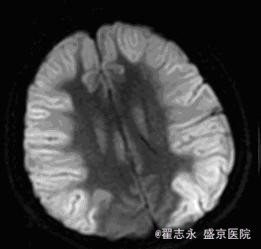

查体:昏迷,瞳孔等大,直径3.5mm,光反射迟钝。四肢疼痛刺激可见收缩反应。余查体不能配合完成。 头MRI的Flair及DWI如图。

诊断:缺血缺氧性脑病

新生儿缺血缺氧性脑病的早期表现有广泛脑水肿、颅内出血、皮质下及脑室旁白质损害、丘脑及基底节区和脑干背侧异常信号等; 晚期可表现为脑室周围脑白质软化症、分水岭区脑损伤等。而成人早期( 10 d 内) MRI 可表现为脑水肿、灰白质分界消失、大脑皮质层层状坏死、颅内出血; 晚期( 10 d~6 个月) 可表现为皮层下白质及深部白质脱髓鞘改变、选择性神经元坏死、广泛脑损害、脑萎缩。